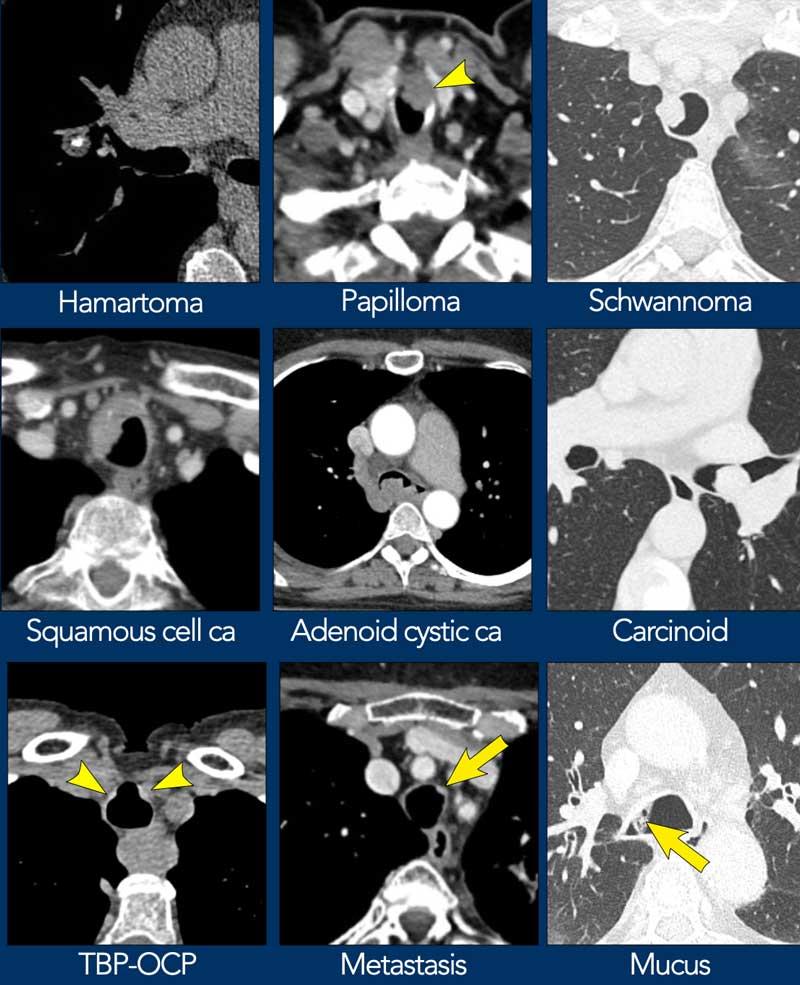

Dưới đây là một số ví dụ về tổn thương dạng nốt hoặc dạng khối trong khí quản và phế quản.

- Ung thư biểu mô tế bào vảy thường có dạng phá hủy với xâm lấn các cấu trúc xung quanh.

- U carcinoid là tổn thương nội phế quản có giới hạn rõ, hiếm khi liên quan đến khí quản.

- Mỡ đại thể có thể gặp trong u hamartoma hoặc u mỡ (lipoma).

- Chất nhầy có tỷ trọng thấp và thường chỉ quan sát được trên cửa sổ phổi.

Dày thành – chẩn đoán phân biệt

Tại vị trí tổn thương, đường bờ bình thường vốn nhẵn và mỏng của thành khí quản và phế quản bị mất đi.

Chỉ một số ít bệnh có đặc điểm hình thái đặc trưng.

Dưới đây là một số ví dụ về dày thành đường thở trung tâm cả dạng khu trú lẫn lan tỏa.

- Viêm đa sụn tái phát có hình ảnh đặc trưng dạng móng ngựa.

- Bệnh amyloidosis biểu hiện dạng không đều rõ rệt kèm vôi hóa, gần như có tính chất đặc hiệu bệnh.

- Tổn thương do xạ trị giới hạn trong trường chiếu xạ.